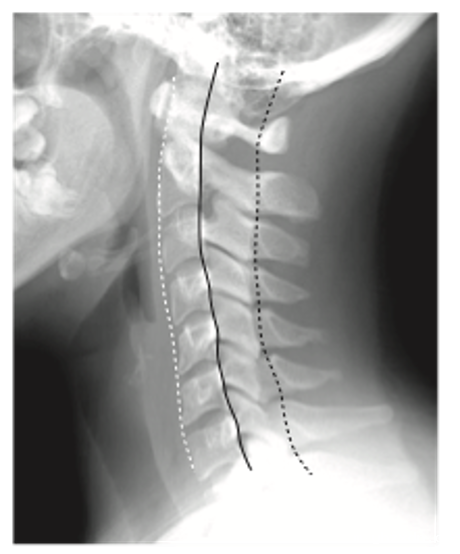

常用的是颈椎X线片,可以显示颈椎退化的严重程度。正常的颈椎存在前弓的生理曲度(图1)。

图1. 正常颈椎X线:颈椎正常生理曲度

早期的颈椎退变X线主要表现为颈椎生理曲度的异常,包括生理曲度变小、消失,甚至反弓。

临床上,部分无症状或者慢性肩背痛的年轻患者常见的异常X线表现就是颈椎曲度变直。